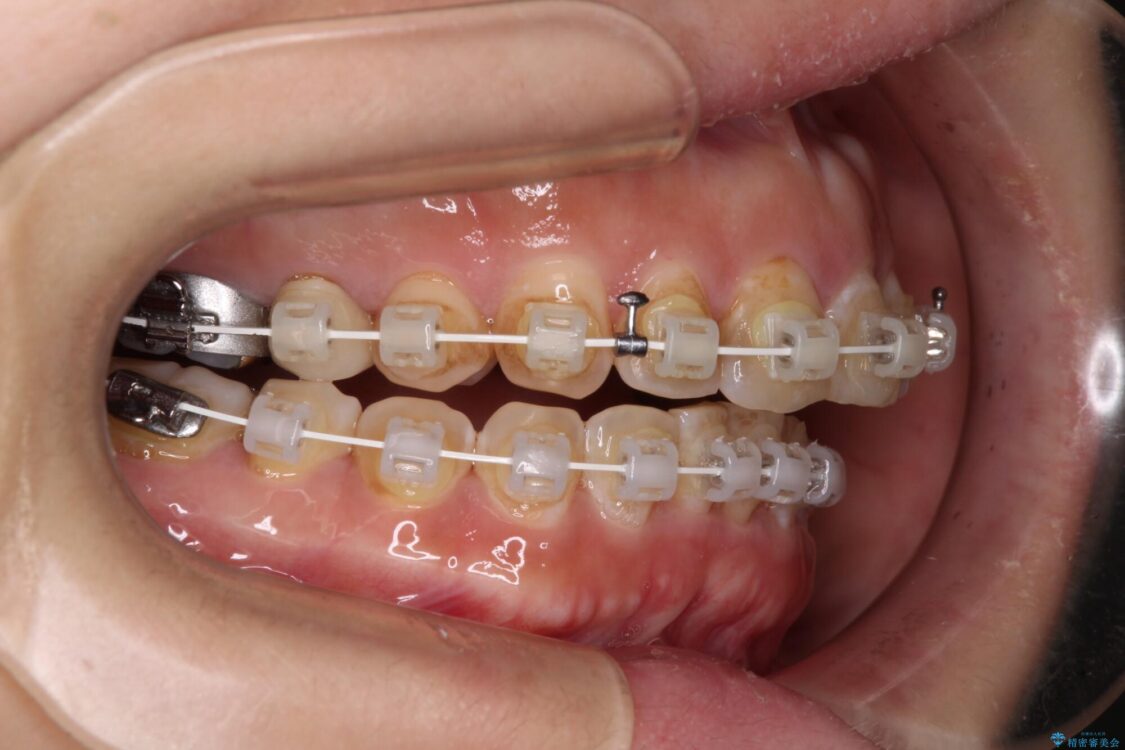

飛び出た上の前歯を気にして来院された患者様です。

なるべく早めに治療を終えたいとのことで、補助装置を用いて上顎臼歯を後方に移動させ、同時にワイヤー装置にて整えることとしました。

舌の突出癖が原因で上下の歯に大きなスペースが生じていたため、舌のトレーニングをしっかり行っていただくことで、上顎歯列をスムーズに移動させることができました。

治療途中